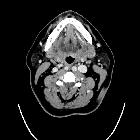

Kissing

carotids: a lovely term for an anatomic variant with great clinical significance. This axial MDCT image shows the level where the two ICA (arrows) are situated in the retropharyngeal space and in close proximity (4mm). The right ICA is more hyperdense than the left due to artefacts.